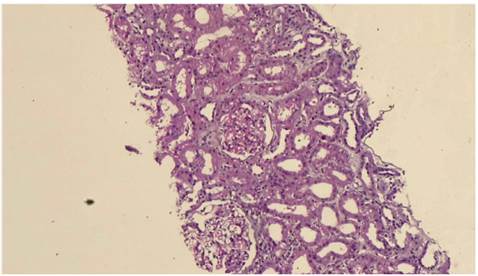

A 22-year-old male patient who had no pathologic antecedents in his medical record presented fever, olfactory amnesia, dysgeusia, diarrhea and anasarca at the time of admission to our healthcare center. After performing a PCR for SARS-CoV-2, the result came back positive. Among the laboratory studies carried out, elevated serum lactate dehydrogenase values (LDH, 274 U/L), hypercholesterolemia (261 mg/dl) and hypoalbuminemia (2.6 g/dl) can be highlighted. By contrast, creatinine test(1 mg/day) and uremia (38 mg/day) levels were normal. Additionally, the virus test panel for human immunodeficiency virus (HIV), hepatitis B (HBV), hepatitis C (HCV), cytomegalovirus (CMV) and Epstein-Barr virus (EBV) was negative. The tests for the immunological markers pANCA, cANCA, ANAS and anti-DNA were negative, and complement component levels were normal: C3 116 mg/dl (88-165 mg/dl) and C4 16.4 mg/dl (14-44 mg/dl). PLA2R antibody was not measured since it was not available. However, severe proteinuria was present (26 g/day). Urotomography revealed normal kidneys and pleural effusion. A diagnosis of pneumonia caused by SARS-CoV-2 and nephrotic syndrome was made. Treatment with furosemide (40 mg/day), enalapril (10 mg/day), spironolactone (25 mg/day) and atorvastatin (10 mg/day) was initiated, and kidney biopsy was performed. Light microscopy revealed eight glomeruli showing glomerulomegaly without any evidence of fibrous or cellular crescents. A pattern of minimal changes in the absence of any remarkable glomerular abnormality was identified, except for one observed glomerulus that presented segmental mesangial proliferation. Furthermore, no abnormalities in the basement membranes, duplication, spicules or double contour were identified. Alterations in the tubules, vessels, and interstice were not observed. Direct immunofluorescence studies revealed no immunoglobulin or complement deposits (Figures 1 and 2). From the ultrastructural point of view, it was possible to demonstrate changes associated with podocyte foot fusion in >80 % of the basal membrane extension, which constituted a diffuse podocytopathy (Figure 3). Two weeks later, the patient showed spontaneously significant proteinuria (0.5 g/dia), edema reduction, as well as negative PCR result for SARS-CoV-2 in a new exam, thus he was discharged.

Note: Panoramic vision of a kidney biopsy in which two glomeruli can be observed.

Source: the authors.

Figure 1 Case 1 - Light Microscopy (panoramic image)